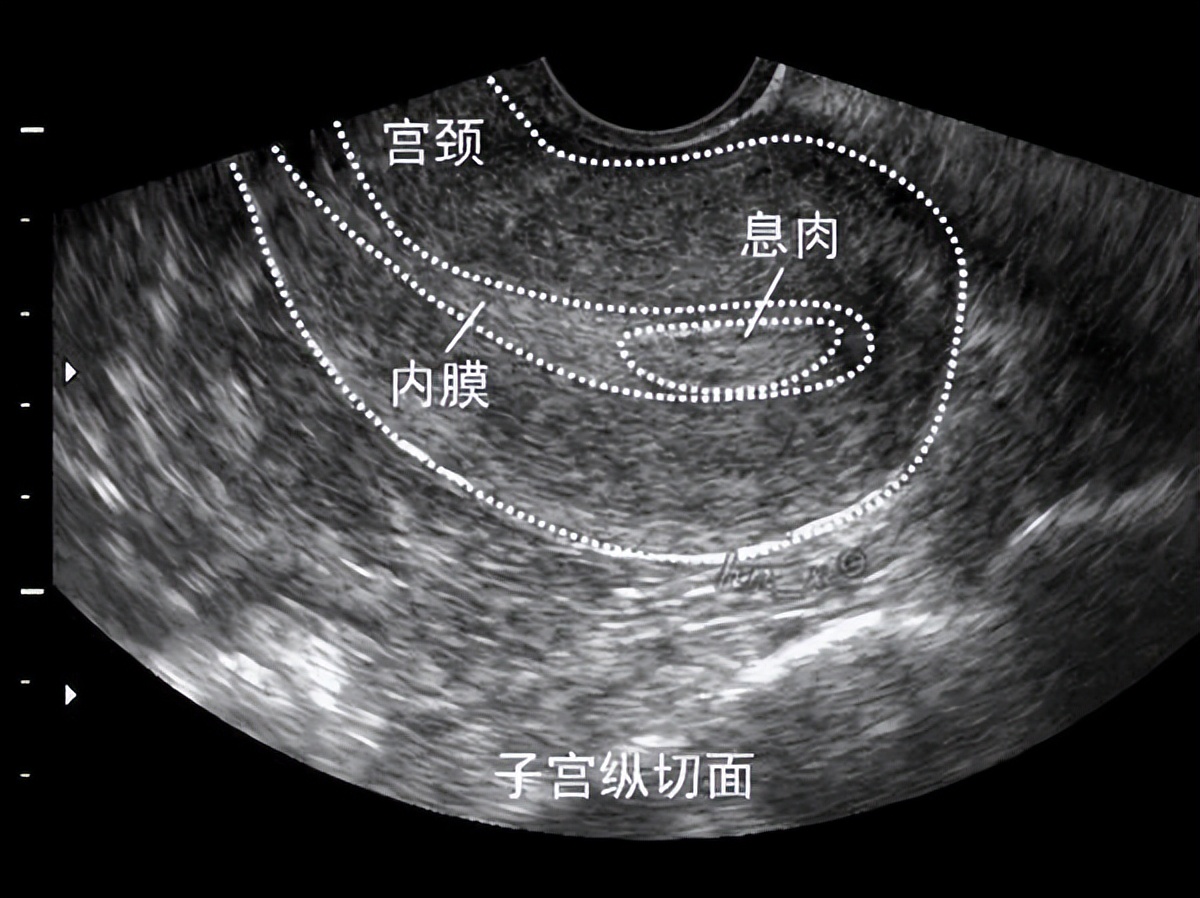

1.超声检查

子宫内膜息肉患者的超声常会提示宫腔内偏高回声。一般建议,发现子宫内膜息肉后于下月月经干净后3天之内复查一下B超或阴超,这是由于子宫内膜增厚等因素可能会干扰B超的影像效果,而且,有的所谓息肉是正常增生的内膜组织;另外,小的息肉有25%的可能随月经来潮脱落。